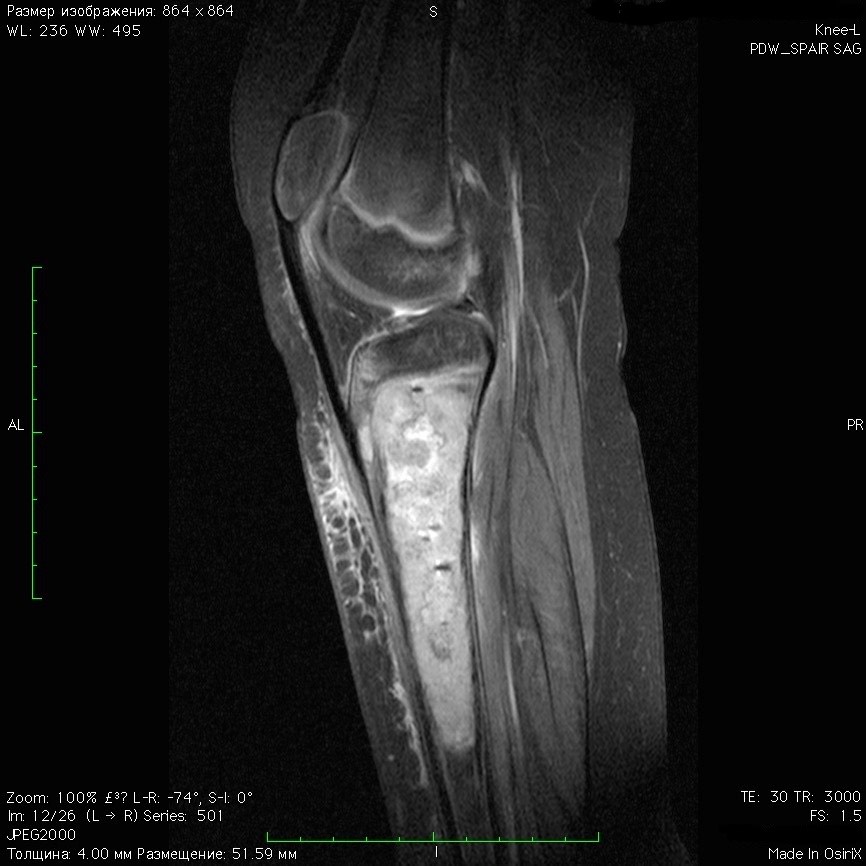

1322. Мальчику 12 лет с жалобами на периодические распирающие боли в верхней трети левой голени, была выполнена МРТ, заболеванием, которое может соответствовать клинико-рентгенологической картине, считают остеосаркому _____ кости